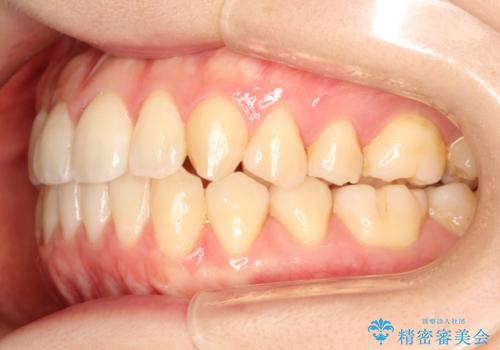

見た目、嚙み合わせ及び、治療期間や施術内容に大変ご満足いただきました。